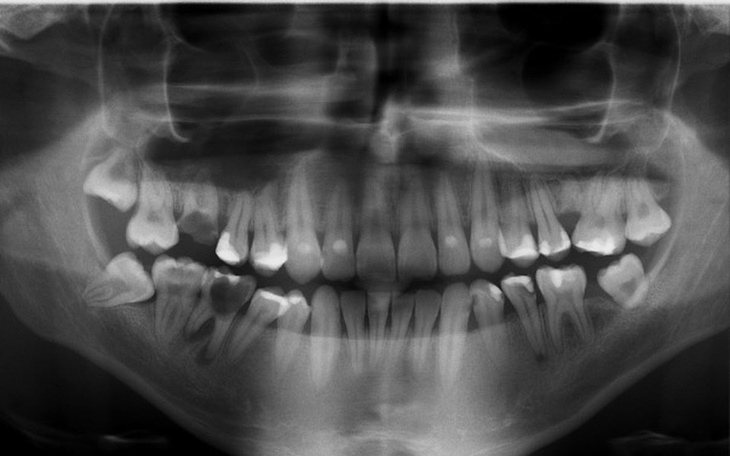

P.S. Zdjęcie zbiórki to mój rentgen